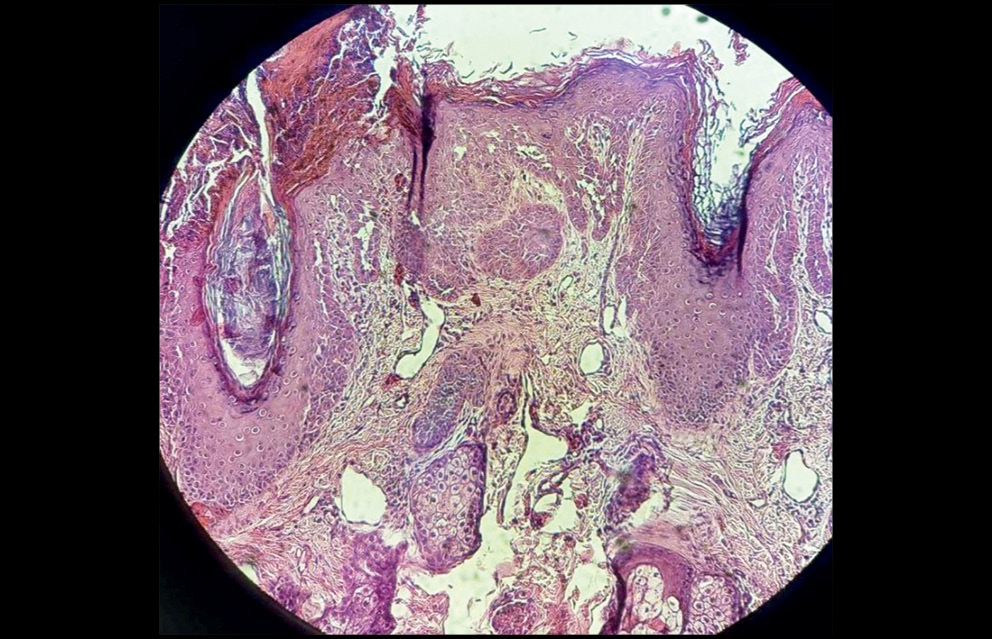

Патоморфологическое исследование биоптата кожи (рис. 5): роговой слой утолщен, фолликулярный гиперкератоз, корки в роговом слое. Участки эрозирования, покрытые детритом. Эпидермис неравномерной толщины, неравномерная гиперплазия зернистого слоя (инфандибулярный тип) и выраженный неравномерный акантоз. Папилломатоз. Надбазальный акантолиз с наличием единичных акантолитических клеток и образованием узких лакун. Встречаются признаки дискератоза в виде единичных круглых тел и кератиновых зерен. Граница с дермой выражена. В дерме сосуды расширены, небольшие скопления лимфоцитов и гистиоцитов, коллагеновые волокна уплотнены очагово, архитектоника нарушена. Заключение: гистологические признаки характерны для фолликулярного дискератоза (болезни Дарье–Уайта).

Рис. 5. Патоморфологическое исследование кожного биоптата. Фолликулярный гиперкератоз, корки в роговом слое. Участки эрозирования, покрытые детритом. Эпидермис неравномерной толщины, неравномерная гиперплазия зернистого слоя (инфандибулярный тип) и выраженный неравномерный акантоз. Папилломатоз. Окраска гематоксилином и эозином, ×10

Fig. 5. Pathomorphological examination of a skin biopsy. Follicular hyperkeratosis, cortex in the stratum corneum. Areas of erosion covered with detritus. The epidermis is of uneven thickness, uneven hyperplasia of the granular layer (infundibular type) and pronounced uneven acanthosis. Papillomatosis. Staining with hematoxylin and eosin, ×10